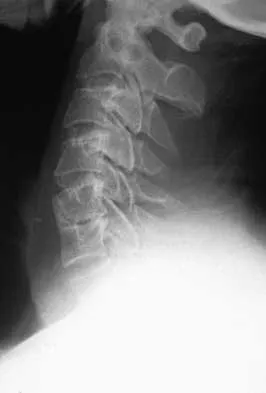

Master AAOS & ABOS boards with high-yield practice MCQs for Set 4, focusing on cervical & thoracolumbar verte…

Master AAOS, ABOS & OITE boards with Set 3 spine surgery MCQs. Covers degenerative spinal conditions, vertebr…

Master AAOS & ABOS boards with high-yield MCQs for Set 2. Review crucial topics like lumbar stenosis, cervica…

Master AAOS & ABOS Spine Surgery boards with Set 1 practice MCQs. Covers degenerative spine conditions, traum…